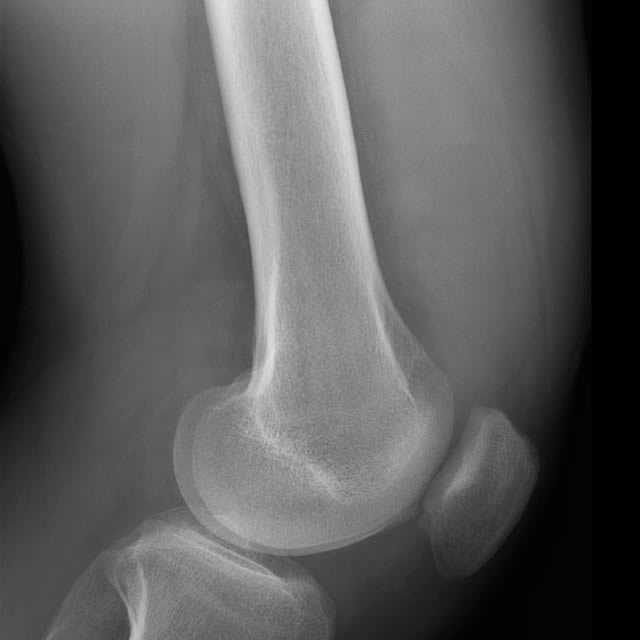

Categorical courses, offering AMA PRA Category 1 Credits™, range from two to five days within the four-week course and provide radiologic-pathologic correlation for both radiology residents and practicing radiologists to show how the underlying pathology of a lesion relates to its imaging appearance.

The mission of these courses is to enable participants to utilize knowledge of how radiology and pathology correlate to improve their diagnostic accuracy in identifying specific diseases, their treatment and potential complications.